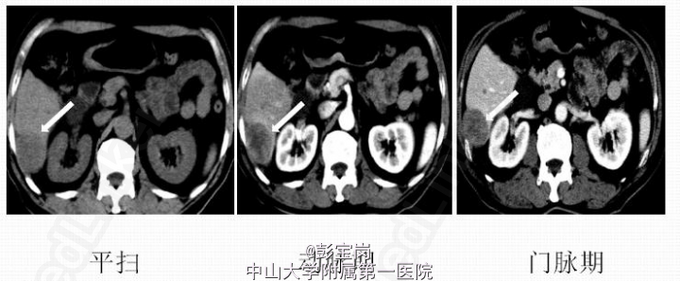

术前诊断:胆囊结石、慢性胆囊炎 处理:腹腔镜胆囊切除术:术中探查胆囊张力大,炎症水肿较明显,壁稍厚,大小约8cm×6cm×2cm,与大网膜粘连。结合术前检查,术中诊断为:胆泥并慢性胆囊炎。术后切开胆囊见豆腐渣样内容物。